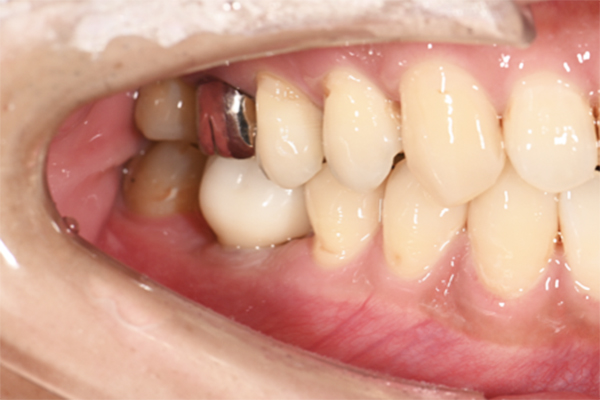

| 主訴 | 歯が痛い |

|---|---|

| 治療内容 | 右上奥歯に対するインプラント治療 (今後右下に対してもインプラント治療を予定) |

| 治療期間 | 6ヶ月 |

| 治療費 | 44万5千円 |

| 治療 リスク | インプラントを埋入したあと3ヶ月程度待ち時間が必要。 その期間は仮歯を使用していただきます。 |